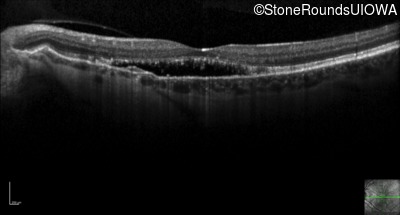

Optical Coherence Tomography - Left - 20/30 -2 sc

Exemplar / OCT Stack

OCT Stack